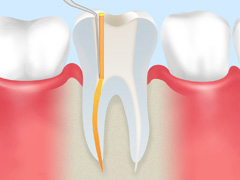

②:計測

感染源の除去や消毒を徹底し、治療の精度向上と再発防止のため、根管内部の深さを計測します。

③:消毒

患部の取り残しを防ぐため、マイクロスコープを使って肉眼では見えないレベルまで消毒を行います。